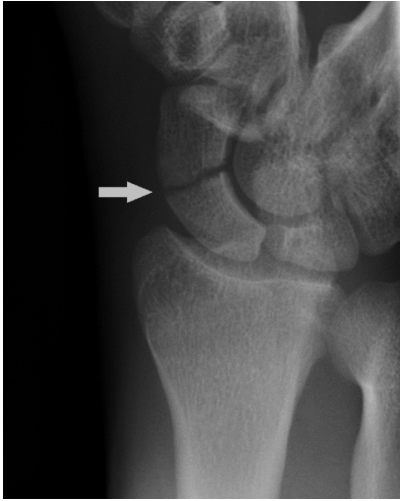

describe what the arrow is pointing at and how it occurs

torus/buckle fracture whereby compressive forces cause one side of bone cortex to buckle and bulge outward whereas the other side remains intact